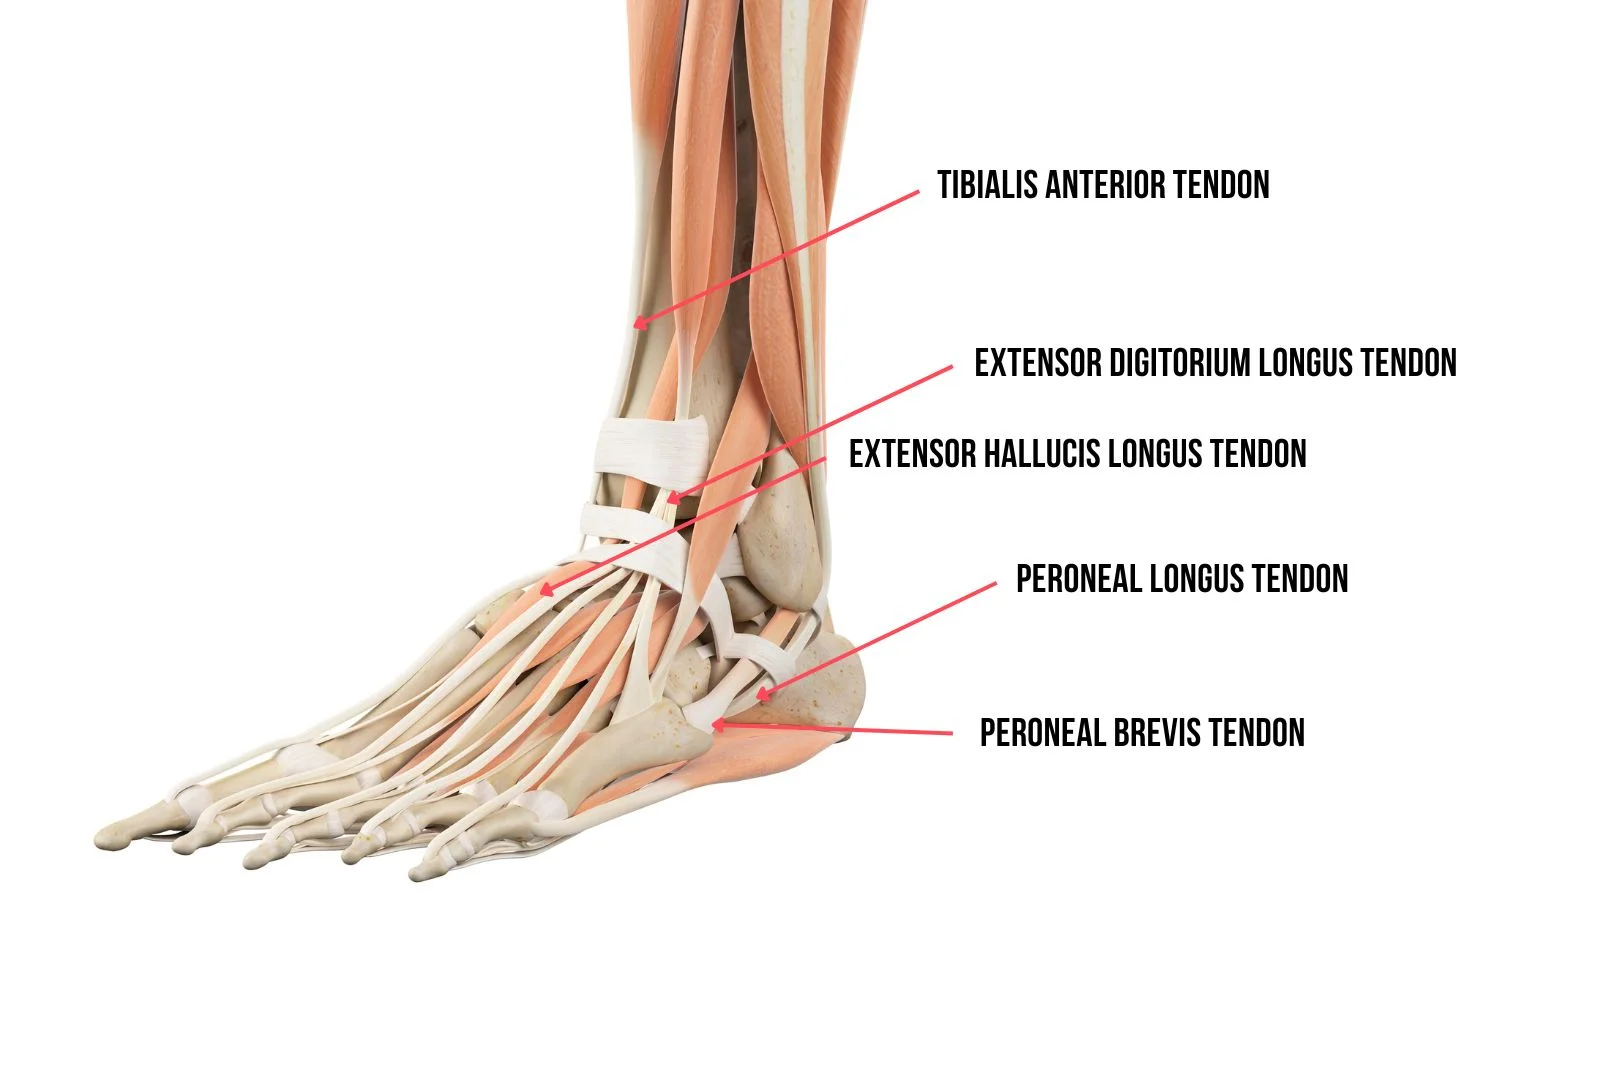

Tendons

Tendons are like strong rubber bands connecting muscles to bones. The Achilles tendon is the largest in the entire anatomy of the ankle and connects the calf muscles to the heel bone. It helps you push off the ground when you walk or run. The other important tendons that are found around the ankle are:

- Tibialis anterior tendon

- Extensor Hallucis longus tendon

- Extensor digitorium longus tendon

- Peroneus longus tendon

- Peroneus brevis tendon